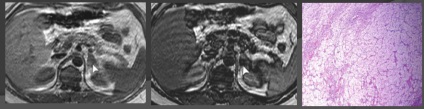

NADPOCHENCHIKOV hiperplazie.

Frecvența în populație de 0,51%, brusc crește odată cu vârsta.

Hiperplazia poate fi nodulara sau pot implica intreaga glanda suprarenală, păstrând forma generală. CT este hipo / ingrosare izodensivnye neted.

Clinica se pot suprapune cu adenom giperfunktsinalnoy.

CT.

Sindromul Cushing. Hiperplazia Makronodulyarnaya cu extinderea glandelor suprarenale (MHMAE) cu denaturarea glandelor suprarenale

CT.

Sindromul Cushing.

Primar pigmentat boala adrenocortical nodular (PPNAD) (*)

MR. T1VI hiperplazie sau adenom.